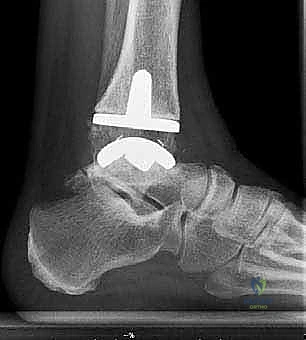

4. تركيب المفصل الصناعي (Implantation)

يتكون مفصل الكاحل الصناعي الحديث عادة من ثلاثة أجزاء:

* قطعة معدنية علوية: تُثبت في عظمة الظنبوب (الساق).

* قطعة معدنية سفلية: تُثبت في عظمة الكاحل.

* قطعة بلاستيكية (بولي إيثيلين عالي الكثافة): توضع بين القطعتين المعدنيتين لتنزلق بسلاسة وتمتص الصدمات، محاكيةً وظيفة الغضروف الطبيعي.

يتم تثبيت هذه الأجزاء بإحكام (إما عن طريق الضغط المباشر لتشجيع نمو العظم حولها، أو باستخدام أسمنت طبي خاص).